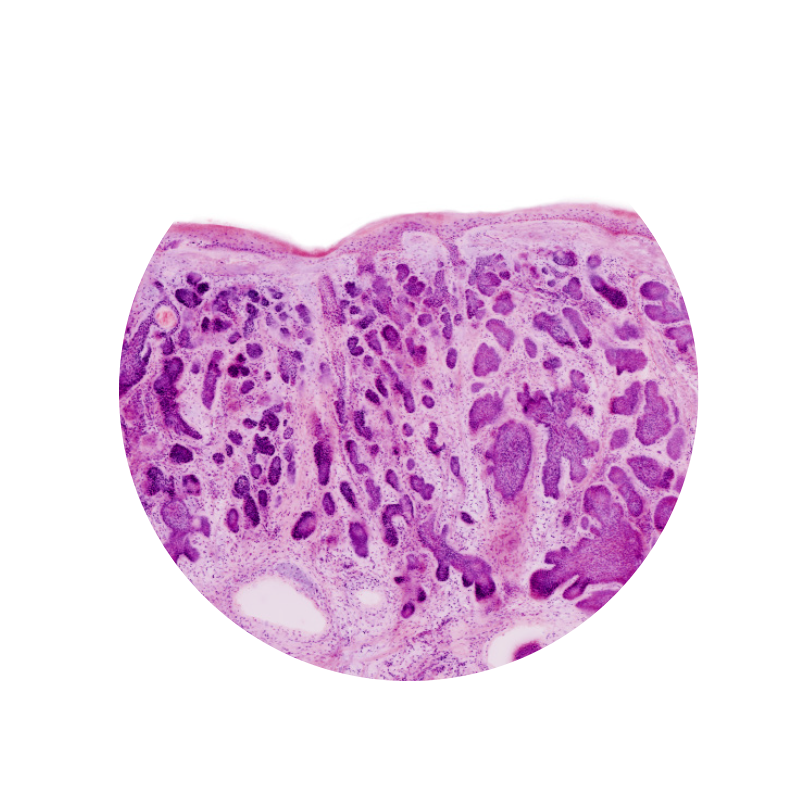

Image courtesy of Dr. Anna Crescenzi, Department of University Hospital Campus Bio-Medico, Rome.